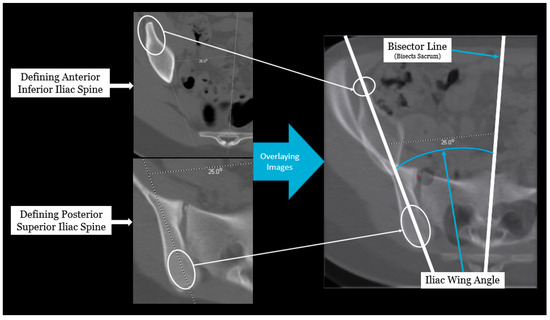

Axial pelvic asymmetry was evaluated with respect to the supra-acetabular region of bone using two landmarks for the iliac wing and sacral ala each. We identified two landmarks for iliac wing which utilized the supraacetabular osseous corridor connecting the anterior inferior iliac spine and the posterior superior iliac spine. For the sacral ala, the highest points of the medial and lateral peak of each hemi-sacrum were used. We used the highest points of the sacral ala as these may represent the rotational change brought about by the imbalance of muscular forces that may produce uneven medial and lateral peaks for each hemi-sacrum. The deformity was measured using two angles—the iliac wing angle and the sacral ala angle. The aforementioned landmarks for the iliac wing and sacral ala were checked for consistency in each axial slice to best represent them as fixed points in each hemipelvis. This was performed to eliminate or minimize the effects of sagittal and coronal plane obliquity using the “copy to all” function on ISITE (Phillips Imaging Inc.). First, we measured the angle between a line bisecting the sacrum and a line drawn from the midportion of the posterior ilium to the midportion of the anterior inferior iliac spine (ASIS) referred to as the iliac wing angle to assess the iliac wing asymmetry (Figure 1). A second angle was measured between a line across the highest points of the sacral ala and the sacral bisector to assess the sacral ala asymmetry, termed the sacral ala angle (Figure 2). The larger of the two angles was considered externally rotated while the smaller angle was considered internally rotated. For each hemipelvis, external/internal rotation (ER/IR) of the iliac wing and sacral ala were termed iliac wing external (IWE)/iliac wing internal (IWI) and sacral ala external (SAE)/sacral ala internal (SAI) respectively. Absolute differences in ER/IR of the iliac wing and sacral ala for one hemipelvis with the corresponding contralateral hemipelvis of the same subject were termed as iliac wing angle difference and sacral ala angle difference, respectively. Additionally, if the patients with cerebral palsy and neuromuscular scoliosis had a full spine AP radiograph available for the measurement of Cobb’s angle (taken prior to any spinal instrumentation), it was recorded. All radiological measurements were reviewed by two authors (A.N.S and J.Z) of this study. To determine inter-observer reliability, two authors reviewed all the angles and were blinded to each other’s measurements. The first author’s measurements were used for analysis.

Figure 2. Radiographic measurement technique for sacral ala angle.